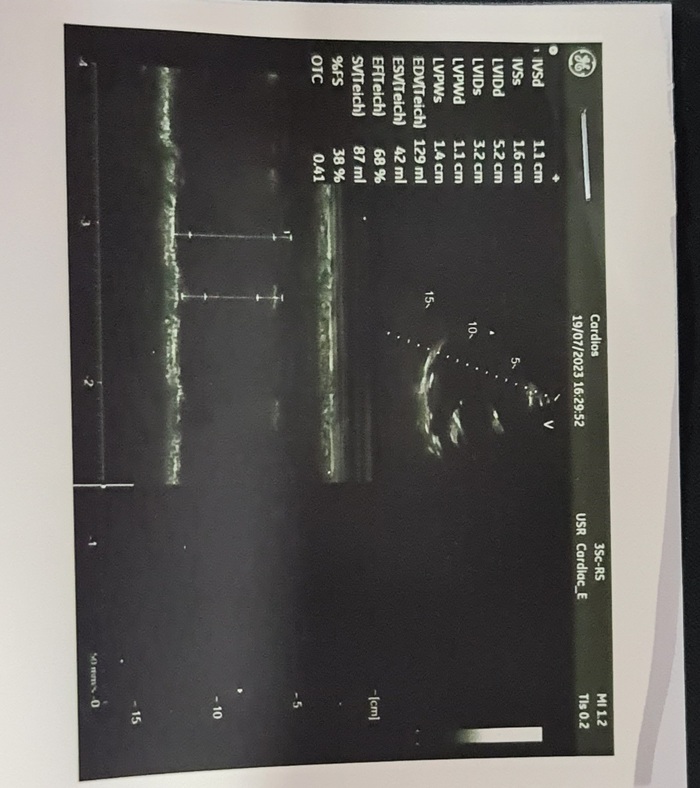

Все доброго времени суток! Мне 39 лет. 2020-ом году переболел ковидом, в целом перенес болезнь нормально, болел только 2-3 дня. Сейчас решил заняться со своим здоровьем, обследоваться. Бросил курить. Недавно обратил внимание, что пульс постоянно в покое в пределах 80-95 (на смарт-часах) и в это время чувствуется легкая слабость, но одышки нет, недавно был у кардиолога. Результаты вложу, кардиолог говорит что все нормально, это особенность организма. Если есть кардиологи в форуме, прошу помочь расшифровать, спасибо.

Показать полностью 5